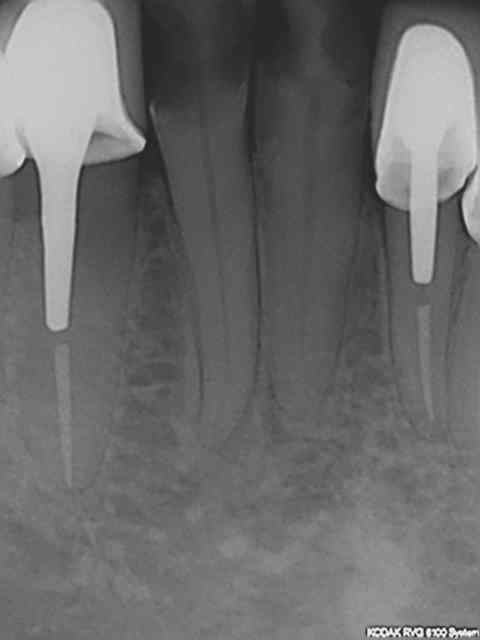

Regardez les endo de chicot29, mono cone et postez vos endo thermo et on compare !

Et effectivement un cone en 6 % n'a rien à voir avec un cone en 2%. L'efficacité tu la vois avec le temps, et un bon mono-cone scellé à l'apex donne des résultats plus que corrects. Je thermo-compacte au machtou quand je fais l'empreinte dans la séance de l'endo)))))

R1 c2o32p - Eugenol

R2 b6cnxj - Eugenol

R3 qrzatb - Eugenol

R4 dqlzan - Eugenol